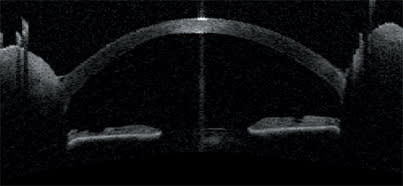

This is an external view of an experimental intracorneal implant (AcuFocus inlay) for the correction of presbyopia.

The Visante OCT shows the flap made for implantation of the intracorneal refractive implant. The surgeon can visualize the implant's edge and the light coming through its fenestrations.

The anterior-segment profile includes the iris and the angle for precise location of the intracorneal implant.

The Visante OCT also is proving to be useful in association with intracorneal refractive implants. The OCT images on this page depict an ultra-thin intracorneal implant currently being evaluated in patients for the correction of presbyopia (AcuFocus Inc.). Based on small-aperture optics, an optimized pinhole, the implant is 3.80 mm in diameter and has a 1.60-mm aperture.

The Visante OCT's high-resolution corneal scan and anterior-segment scan pinpoint the location of the implant and allow measurement of its diameter and thickness.